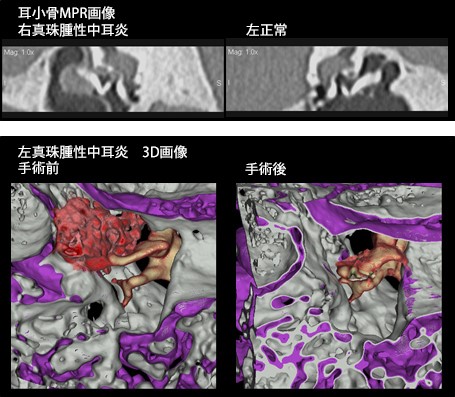

64列の強みを生かし、短時間での撮影を行うことで患者さんの負担を軽減し、耳の疾患に対しては0.5m撮影にて、微細な構造を描出します。また、被曝低減フィルターと逐次近似再構成法により、小児でも極低線量ながら、診断に十分な画像を提供します。

耳鼻科領域 多断面再構成(MPR)

耳小骨や腫瘍等の、より高精細な3次元画像を提供しています。

3次元画像(3D)